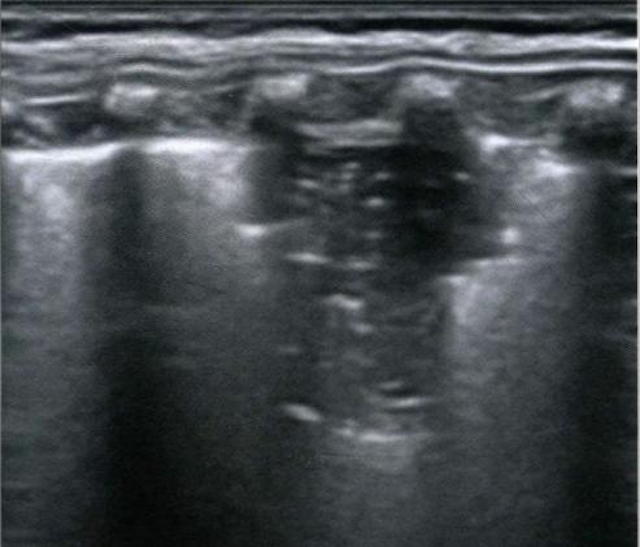

肺变实超声图